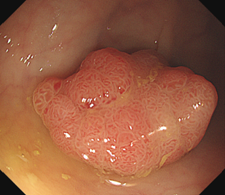

肠息肉大部分是肠黏膜的一个新生物,若是恶性,危害自不必说。

肠道息肉分为非腺瘤性息肉和腺瘤性息肉。

腺瘤性息肉是公认的癌前病变

目前的内镜技术发展,肠镜下切除息肉成为非常简便、安全、有效的微创操作。

让我们通过肠镜下,来了解一下息肉切除的几个步骤:

步骤一:发现息肉,并将其暴露于视野正中;